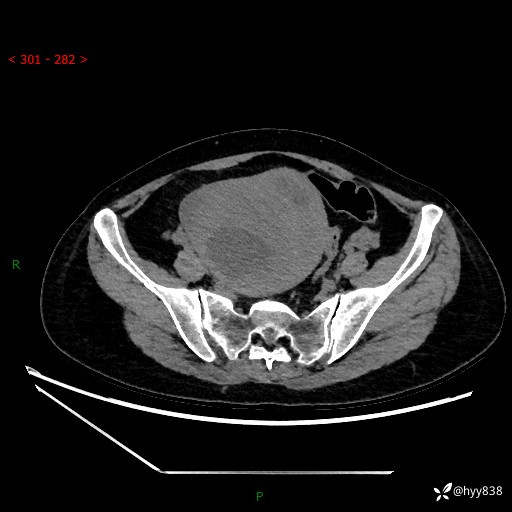

辅助检查:CT

增强(动脉期+静脉期)